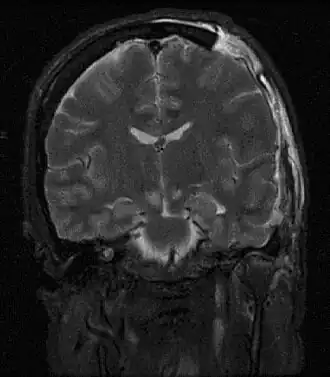

| Imagem por ressonância magnética de lesões causadas por uma hérnia cerebral | |